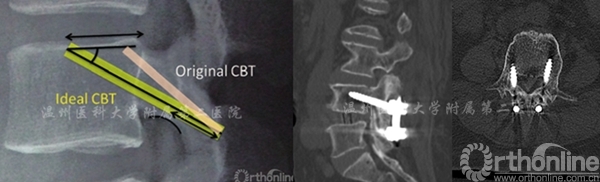

同时理想的生物力学轨迹对于CBT以获得更好的固定和临床效果至关重要:

以往的生物力学研究发现理想的螺钉轨迹应满足以下几点:

1. 螺纹与皮质骨最大限度的接触;

2. 将螺钉放置在椎体内足够深的位置,以增强固定力并有效分担轴向载荷;

3. 避免与相邻的小关节碰撞。

4. 螺钉从尾端植入;

5. 与椎板内的皮质骨接触;

6. 通过椎弓根的下缘;

7. 螺钉头端朝向上椎骨终板的后三分之一到后半部;

8. 外倾角为25-30°,头倾角8-9°(图7)[7]。

图7 左:理想的皮质骨螺钉轨迹 右:不理想的皮质骨螺钉轨迹(螺钉轨迹偏下、偏内)